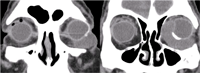

La tomografía computerizada revelaba una masa isodensa respecto al globo ocular, homogénea y bien definida, con extensión desde la región más anterior, temporal e inferior de la órbita, hacia su región medial más posterior, afectando al músculo recto medial y alterando la morfología del globo ocular (

Figura 1).

Figura 1. TC orbitario (cortes coronales). Se aprecia una masa isodensa, homogénea, bien delimitada que rodea el globo ocular izquierdo desde su porción anterior, temporal e inferior hacia región medial más posterior.